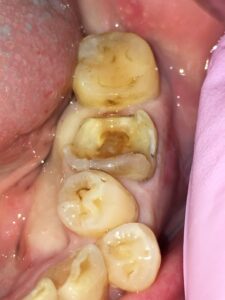

歯に器具をかけると銀歯はすでに浮いており、ポロッととれてきました。幸い銀歯の下にほとんど虫歯はなく、神経までは到達していなかったのでそのまま修復治療を行うことにしました。

欠損が大きいので、一般的にはクラウンで被せて治療することになりますが、できるだけ歯を削らず回数少なく白い材料で治したいという希望があり、ダイレクトボンディングによる修復を行うことにしました。